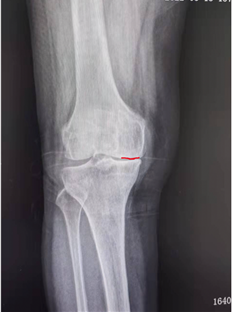

田女士手术前的膝关节X线片,正位可见内侧间室骨对骨(左,红色实线),侧位可见平台前内侧骨磨损(右,红色虚线)